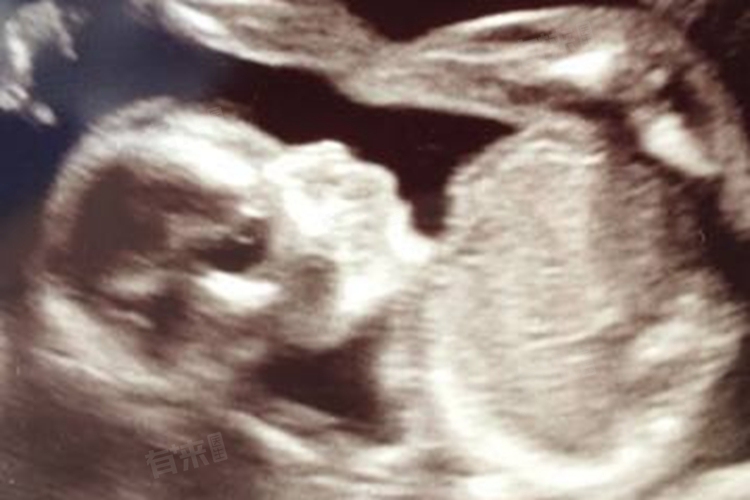

孕31周时,胎儿的体重是评估其生长发育情况的重要指标之一。通常情况下,孕31周胎儿的体重正常范围在1500g-2000g,相当于3-4斤,这一范围内的体重被认为是符合正常生长发育标准的,但具体数值会因个体差异而有所不同。

在产检中,医生通常会通过腹部触诊、B超等手段来估计胎儿的体重。然而,由于受到腹壁厚度、子宫张力、羊水量、胎位等多种因素的影响,估计的体重可能会存在一定的误差。因此,孕妇应该保持理性态度,不要过分纠结于胎儿的体重数值,而是应该关注其整体生长发育情况。同时,如果出现异常情况,建议在医生的指导下进行必要的调整和治疗,以确保胎儿的健康成长。